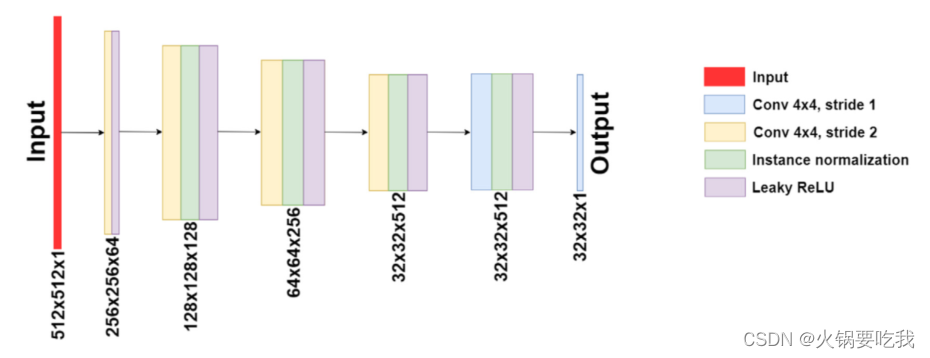

判别器:PatchGAN